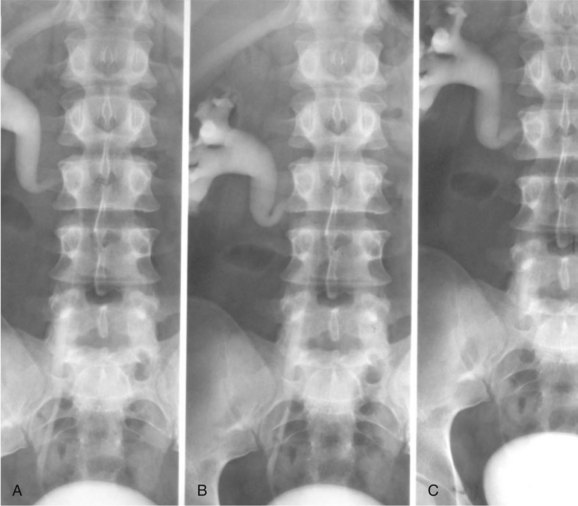

Before the advent of cross-sectional imaging, radiologic diagnosis relied upon imaging not the disease process itself but its secondary effects on the ureters. The classic radiologic findings included medial deviation of extrinsically compressed ureters with hydronephrosis. Medial deviation is a nonspecific finding, because it has been demonstrated in up to 18% of normal subjects (Saldino and Palubinskas, 1972). Hydronephrosis is typically demonstrated on ultrasonography, and there may also be a smooth, well-demarcated, hypoechoic or isoechoic mass anterior to the lumbar or sacral spine (Amis, 1991). Retrograde pyelography typically demonstrates hydronephrosis, with medially deviated and segmentally narrowed ureters without filling defects (Fig. 40–10). Currently, cross-sectional imaging with CT or MRI is the modality of choice for evaluating patients with suspected retroperitoneal fibrosis. Both modalities have been demonstrated to delineate accurately the extent of the disease when correlated with surgical exploration (Mulligan et al, 1989). CT typically reveals a well-demarcated retroperitoneal mass, isodense with muscle on unenhanced studies (Fig. 40–11) (Vivas et al, 2000). It typically surrounds the lower abdominal aorta, inferior vena cava, and iliac vessels—frequently enveloping the ureters. In contrast, masses secondary to malignancy usually displace the aorta anteriorly and the ureters laterally. Variable degrees of contrast enhancement may be seen, typically more pronounced earlier in the course of the disease when the presumably more-immature plaque has increased vascularity (Amis, 1991). Some have advocated noncontrast multidetector CT imaging combined with antegrade CT pyelography for evaluation, because it can define the fibrotic process and the level and degree of ureteral obstruction without administration of intravenous contrast material (Ghersin et al, 2004). However, the invasive nature of this diagnostic approach limits its applicability.

Figure 40–10 Retrograde pyelogram performed in a patient with retroperitoneal fibrosis. Note evenly narrowed midureteral segment with proximal hydronephrosis.

(Courtesy of Dr. Ronald Zagoria.)